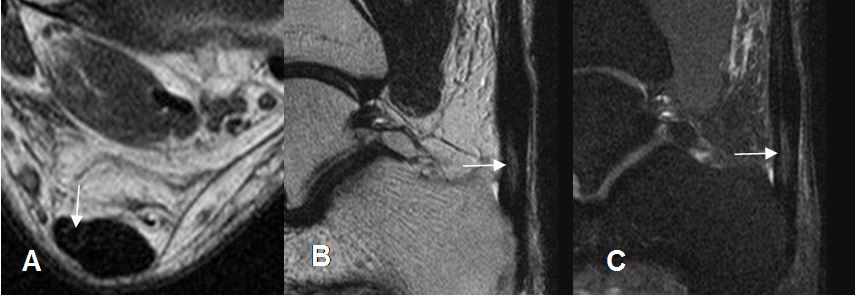

Fig 75. Tenosinovitis de los peroneos.

A: RM axial en T2 y B: RM coronal en STIR. Presencia de líquido rodeando completamente,

los tendones peroneos por tenosinovitis.